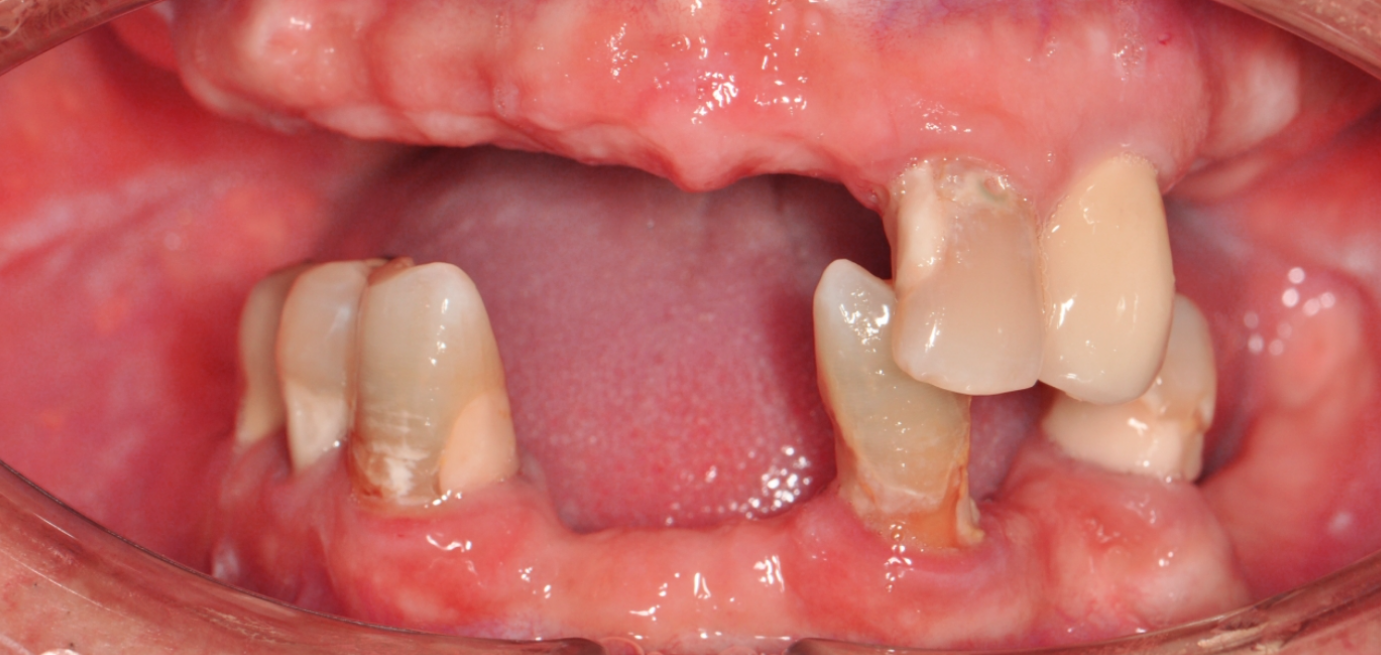

Before & After

Drag Before After

버튼을 움직여서 변화를 확인해보세요.

(서울정석치과는 의료법을 준수하며 위 케이스는 실제 환자의 동의를 얻은 사례입니다.)